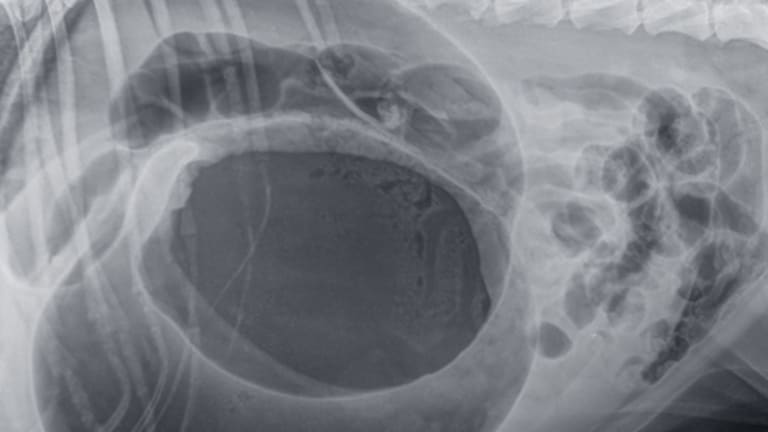

csomorcsavar röntgenkép